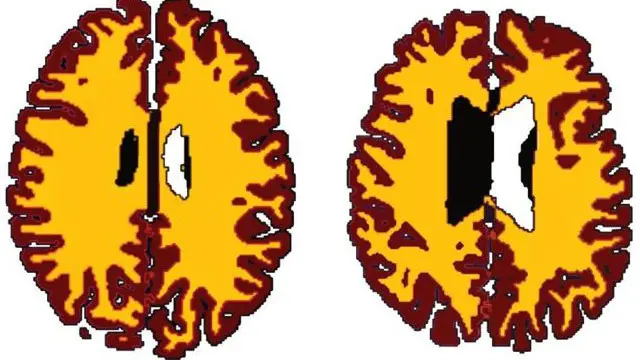

Sumber gambar, Dr Lisa Ronan

Temuan yang diterbitkan di jurnal Neurobiology of Aging menemukan perbedaan berarti volume bagian putih orang kelebihan berat badan dibandingkan yang lebih langsing.

Kelompok gemuk memiliki bagian putih yang jauh lebih sedikit dibandingkan rekan yang lebih kurus.